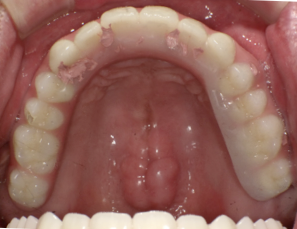

オールオン6本のインプラントをいれました

初期固定もよかったので即時荷重をおこなっています

術後2週間 傷もきれいに治ってきています